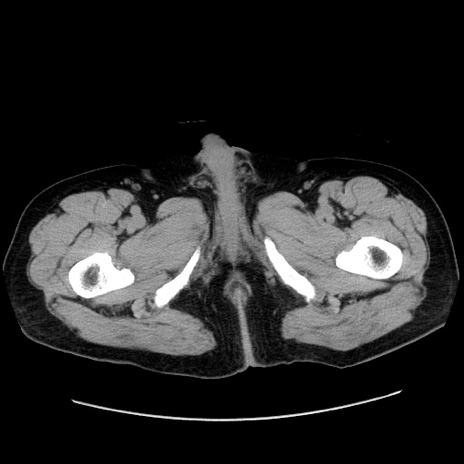

症例30(横断像)

【症例】80歳代男性

【主訴】臍周囲痛

【現病歴】約6時間前から臍下部痛が出現。次第に腹部膨隆・背部痛も生じてきたため来院。背部痛の場所は変化しない。

【身体所見】意識清明、BT 36.3℃、BP  131/87mmHg、P 87bpm、SpO2 100%(RA)、臍周囲自発痛・圧痛あり、反跳痛なし、自発痛部位に一致して板状硬あり、腹部膨隆、腸雑音減弱、CVA tenderness両側陰性。